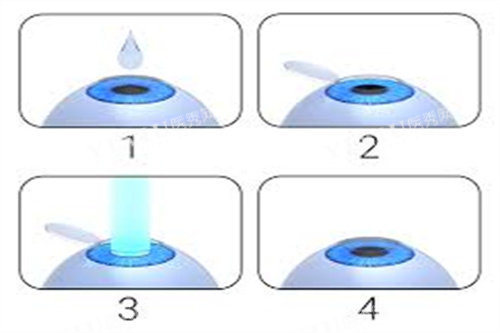

半飞秒手术:个性化定制

半飞秒技术结合飞秒激光制瓣与准分子激光切削,价格更具弹性。标准半飞秒手术约8800-12800元,个性化方案(如德国蔡司设备)则达12800-15800元。青岛分院数据显示,部分患者选择高端套餐后总费用接近18000元。